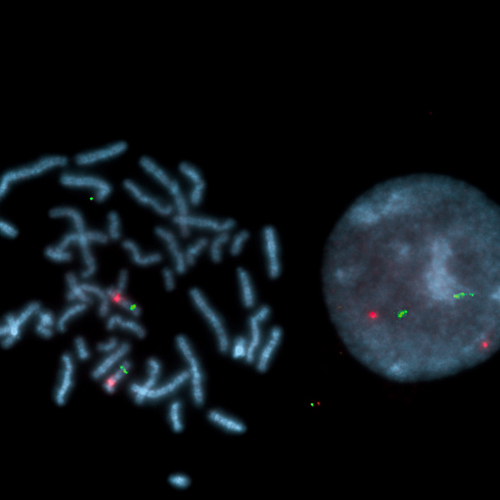

KBI-20003R

SE 3 (D3Z1) Red